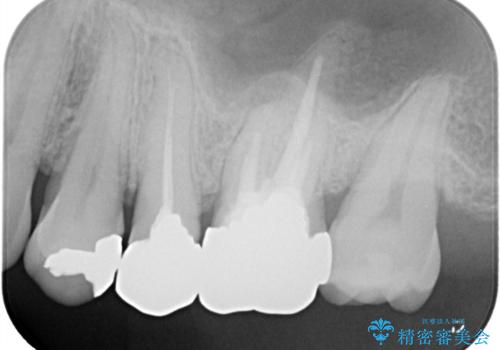

- お口の中にある銀歯を全てなくして、白く健康的な状態にしたい」という主訴でご来院されました。長年使用してきた複数の銀歯は、経年劣化により適合が悪くなっており、一部では内部で二次カリエス(虫歯の再発)も認められました。

患者様と相談の上、全ての金属(メタル)を取り除き、生体親和性が高く審美性に優れた素材へ置き換えるメタルフリー治療の計画を立案。部位や欠損の大きさに合わせ、セラミックインレーおよびセラミッククラウンを用いて、お口全体の調和を整えることとしました。

銀歯の除去と精密な再治療: 古い銀歯を一つひとつ丁寧に取り外し、内部の虫歯を徹底的に除去。神経を保護するための処置を行った上で、適合性を極限まで高めるために精密な型取りを行いました。

オールセラミックによる修復: 天然歯のような光の透過性と硬さを持つオールセラミックを使用しました。奥歯であっても、患者様固有の歯の色調や咬み合わせの溝を忠実に再現した修復物を装着。金属を一切使用しないことで、金属アレルギーのリスクを排除し、歯肉の色が黒ずむ心配もなくなりました。